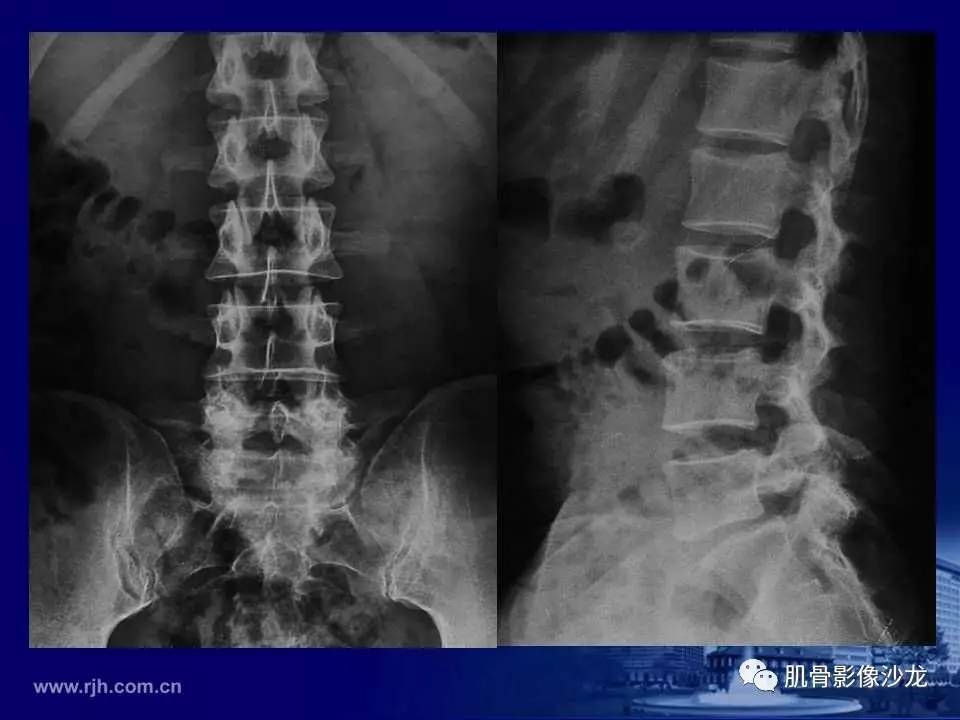

強直性脊椎炎の写真

強直性脊椎炎は主に脊椎の関節に影響を与えます。医療画像は、炎症や損傷の一部と、それらがどのように症状につながるかを確認するのに役立ちます。

強直性脊椎炎(AS)は、脊椎の関節に炎症を引き起こし、痛みを引き起こす関節炎の一種です。 AS は、脊椎の基部と骨盤が接する仙腸関節 (SI) に影響を与えることがよくあります。

強直性脊椎炎では​​何が起こりますか(写真)?

また、脊椎を内側から調べるために、X線やMRIスキャンなどの検査を受けることもあります。血液検査では、HLA-B27 遺伝子と炎症マーカーがあるかどうかを判断できます。